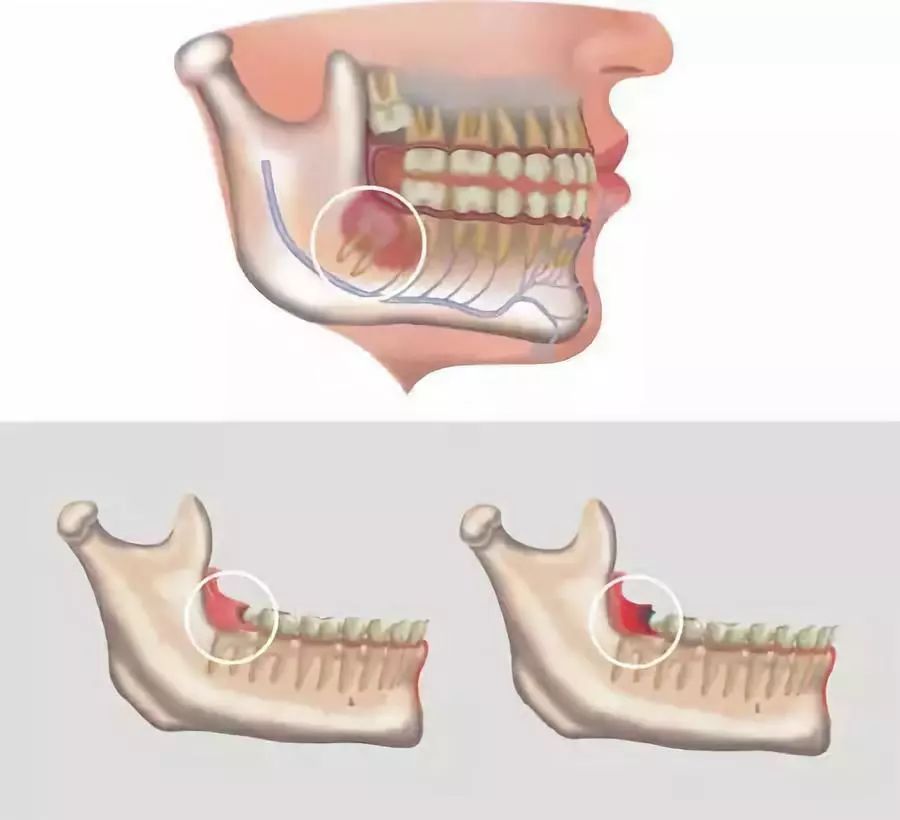

智齿冠周炎

智齿无法完全萌出时,和牙床之间的缝隙是十分容易进食物残渣的,关键是进了还不出来,这个时候就容易造成局部的感染~

并且容易在抵抗力相对低下时、加班顾不上刷牙时、学习忙碌压力大时等关键时刻反复发作,非常耽误事。